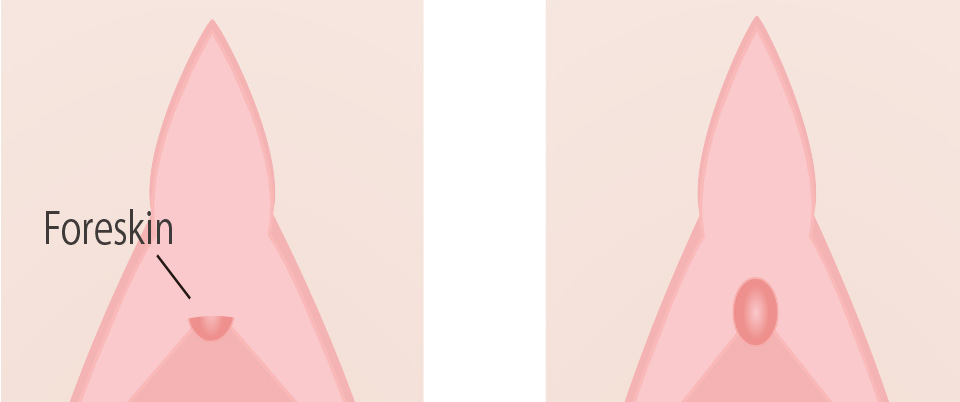

On the outside of the clitoris, there is a skin called the foreskin, and when this skin covers the entire clitoris, it is called a clitoral foreskin. Secretions and dirt accumulate, causing odor and unsanitary conditions, which can lead to pain and insensitivity during intercourse.

Surgery is performed to remove the skin covering the clitoris to make it easier to expose the clitoris.

Recommended for people with these problems